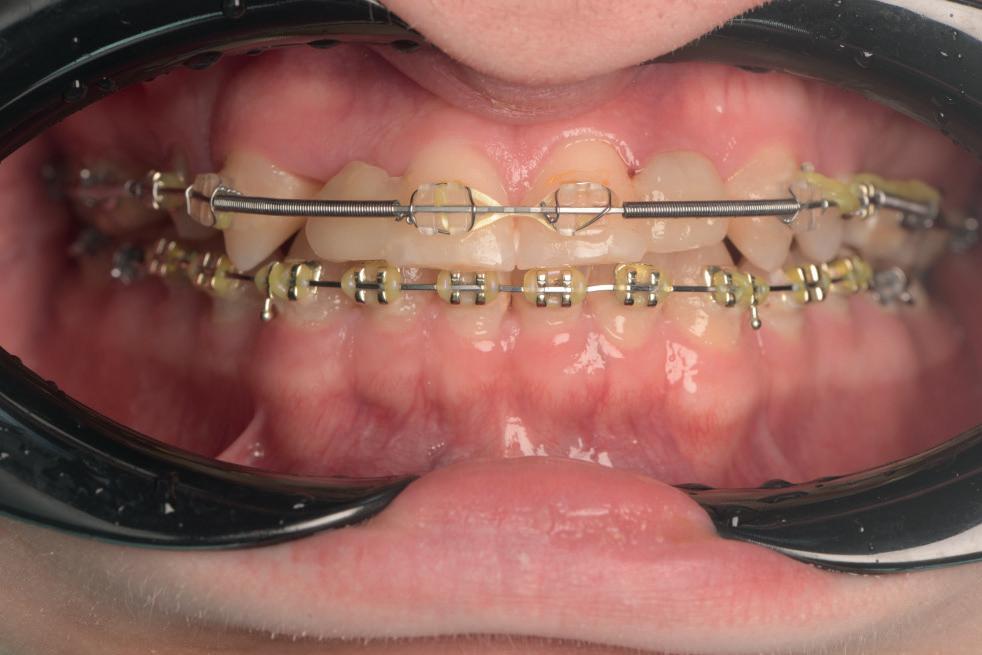

CASE STUDY

Guided implant approach for reproducible results, page 28

1. Adaptable to different guided surgery protocols: piloted, semi-guided or fully guided.

2. No friction between drills and guide sleeve, no overheating and no release of particles.

3. No specific drills and a very small surgical box.

4. Full control of drilling depth.

5. Your conventional driver-guided drilling sequence.